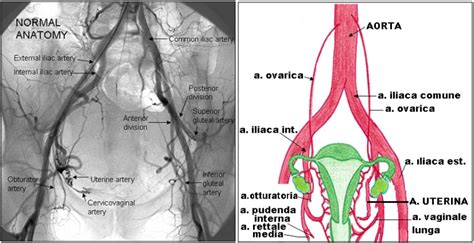

- Embolizzazione dell'arteria uterina (EAU): È una tecnica guidata dall'immagine che mira a causare l'infarto dei fibromi, preservando il tessuto normale uterino. Si iniettano particelle emboliche per occludere l'apporto di sangue ai fibromi. I dati della letteratura mostrano un elevato tasso di successo, con riduzione del volume e miglioramento della sintomatologia nel 75-85% dei casi. Le donne che considerano un'ulteriore gravidanza devono essere informate che l'embolizzazione dell'arteria uterina può aumentare alcune evoluzioni ostetriche, tra cui l'aborto spontaneo, il parto cesareo e l'emorragia post-partum.